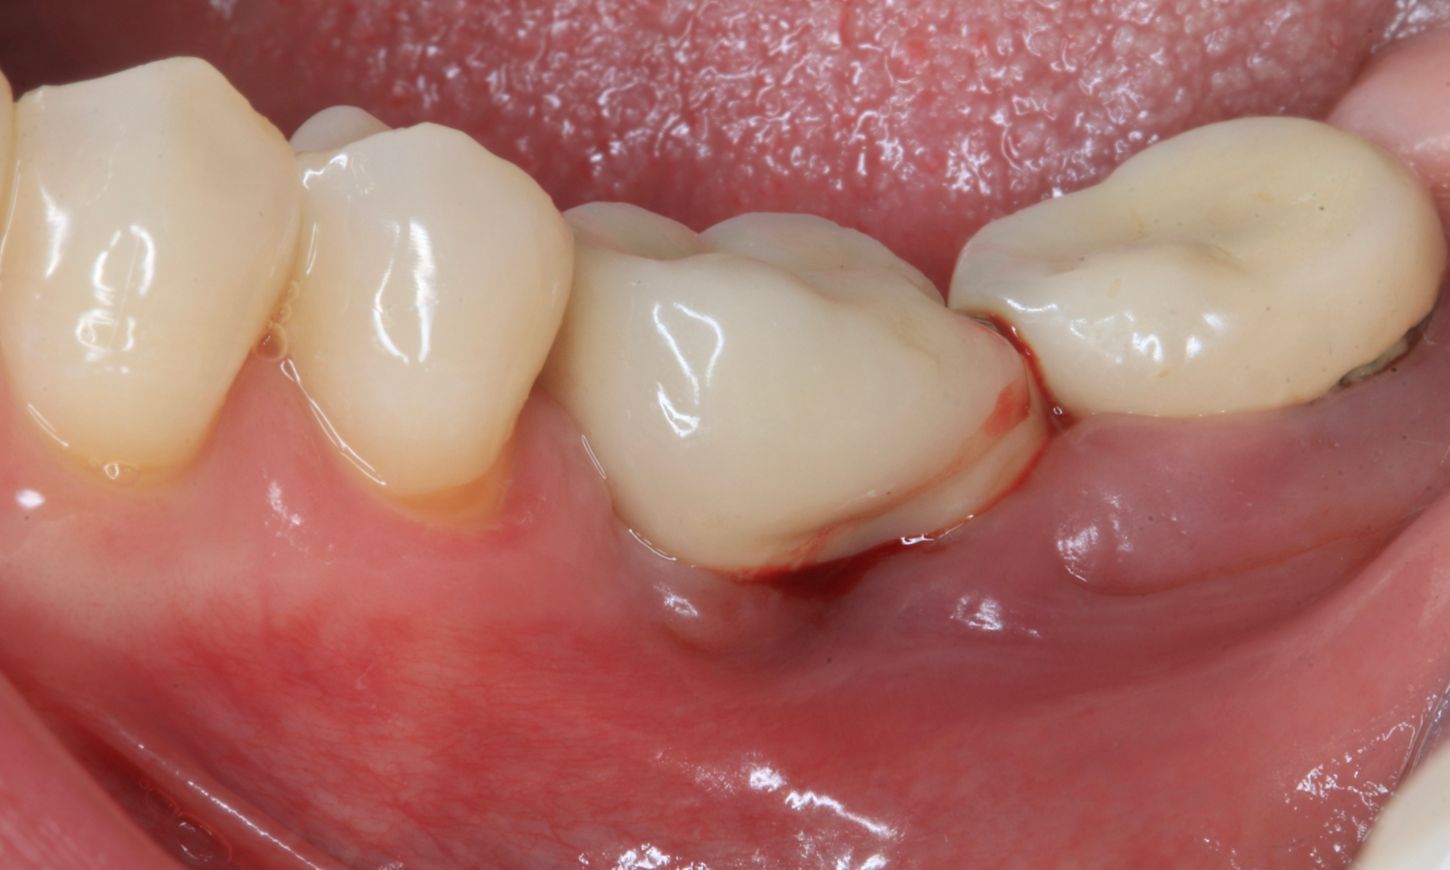

After the non-surgical treatment, clinical examination in 2021 showed a decrease in inflammation, though it was not completely resolved (Fig. 2). Lidocaine 2% with epinephrine 1:100,000 was administered. Upon removal of the prosthesis, the peri-implant mucosa surrounding the implants in positions #36 and #37 exhibited localized inflammation with evident redness, swelling and bleeding (Fig. 3).

Fig. 2

Fig. 3